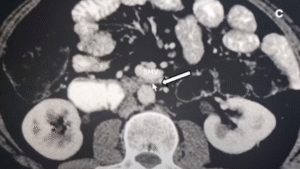

Image: from Yetişir [1] shows an interposition of the mesenteric vein in between the superior mesenteric artery and the duodenum

The paper from Yetişir [1] shows the mesenteric vein interposed between the superior mesenteric artery and the duodenum. Consequently, both vessels exert compression on the duodenum. However, the images supporting the diagnosis in the paper suggest that some of the compression attributed to the superior mesenteric vein may actually originate from the jejunal vein branch behind the superior mesenteric artery. This condition is not uncommon. Nevertheless, the paper only contains one image demonstrating the dumbbell-shaped mesenteric vein dorsal to the superior mesenteric artery.